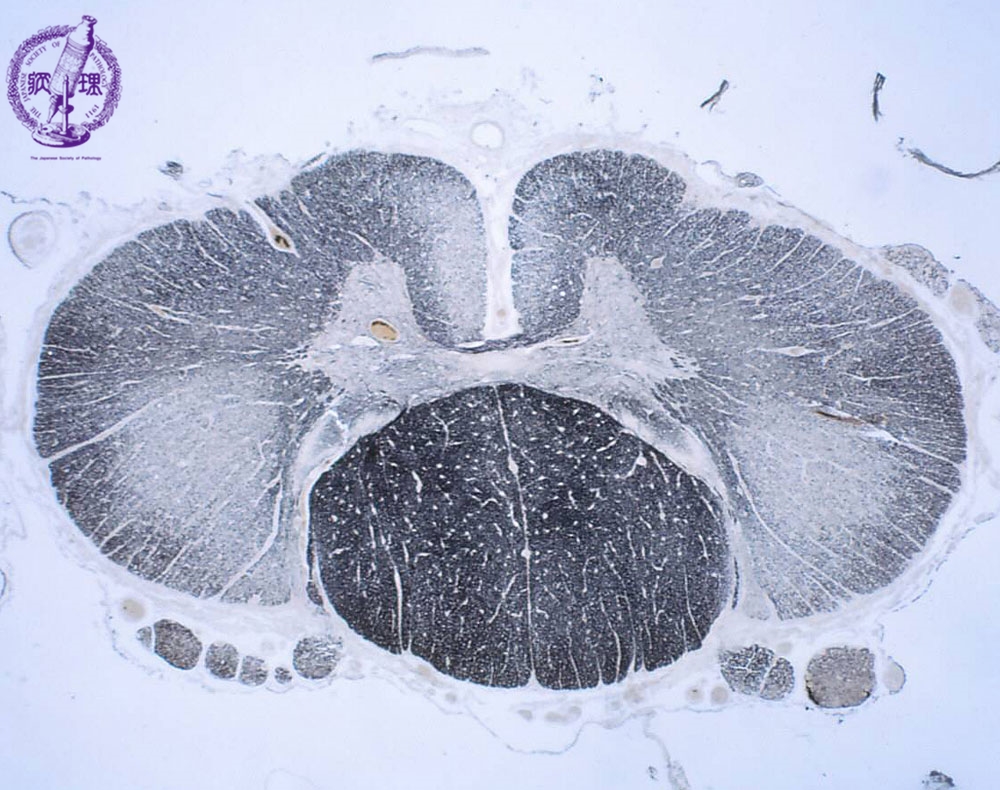

- (7)Amyotrophic lateral sclerosis (ALS)

Microscopic findings (Kultschitzky staining): Marked symmetrical demyelination (whitening regions) was detected in the anteriolateral roots (especially pyramidal tract) of the spinal cord (arrows). The posterior roots were well preserved.